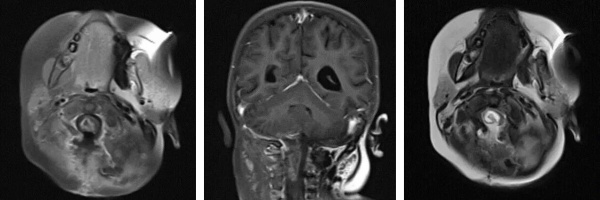

術(shù)前影像(MRI)

懷著最后一線希望,阿什利一家跨海越洋,來到我院腦腫瘤科求助。入院時,患兒右側(cè)肢體活動嚴重受限,面癱癥狀逐漸顯現(xiàn)。影像檢查顯示腫瘤位于腦干中央,與周圍重要神經(jīng)結(jié)構(gòu)和血管關(guān)系密切,手術(shù)難度極大、風險極高。